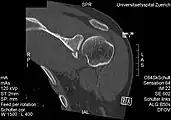

CT scan showing a bony Bankart lesion at the antero-inferior glenoid